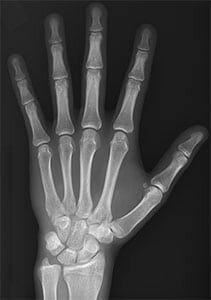

• Rayos X

Rayos X

El 8 de noviembre se celebra cada año el Día Internacional de la Radiología. Esta fecha conmemora el día en que el profesor Wilhelm Conrad Röntgen descubrió los rayos X en 1895.